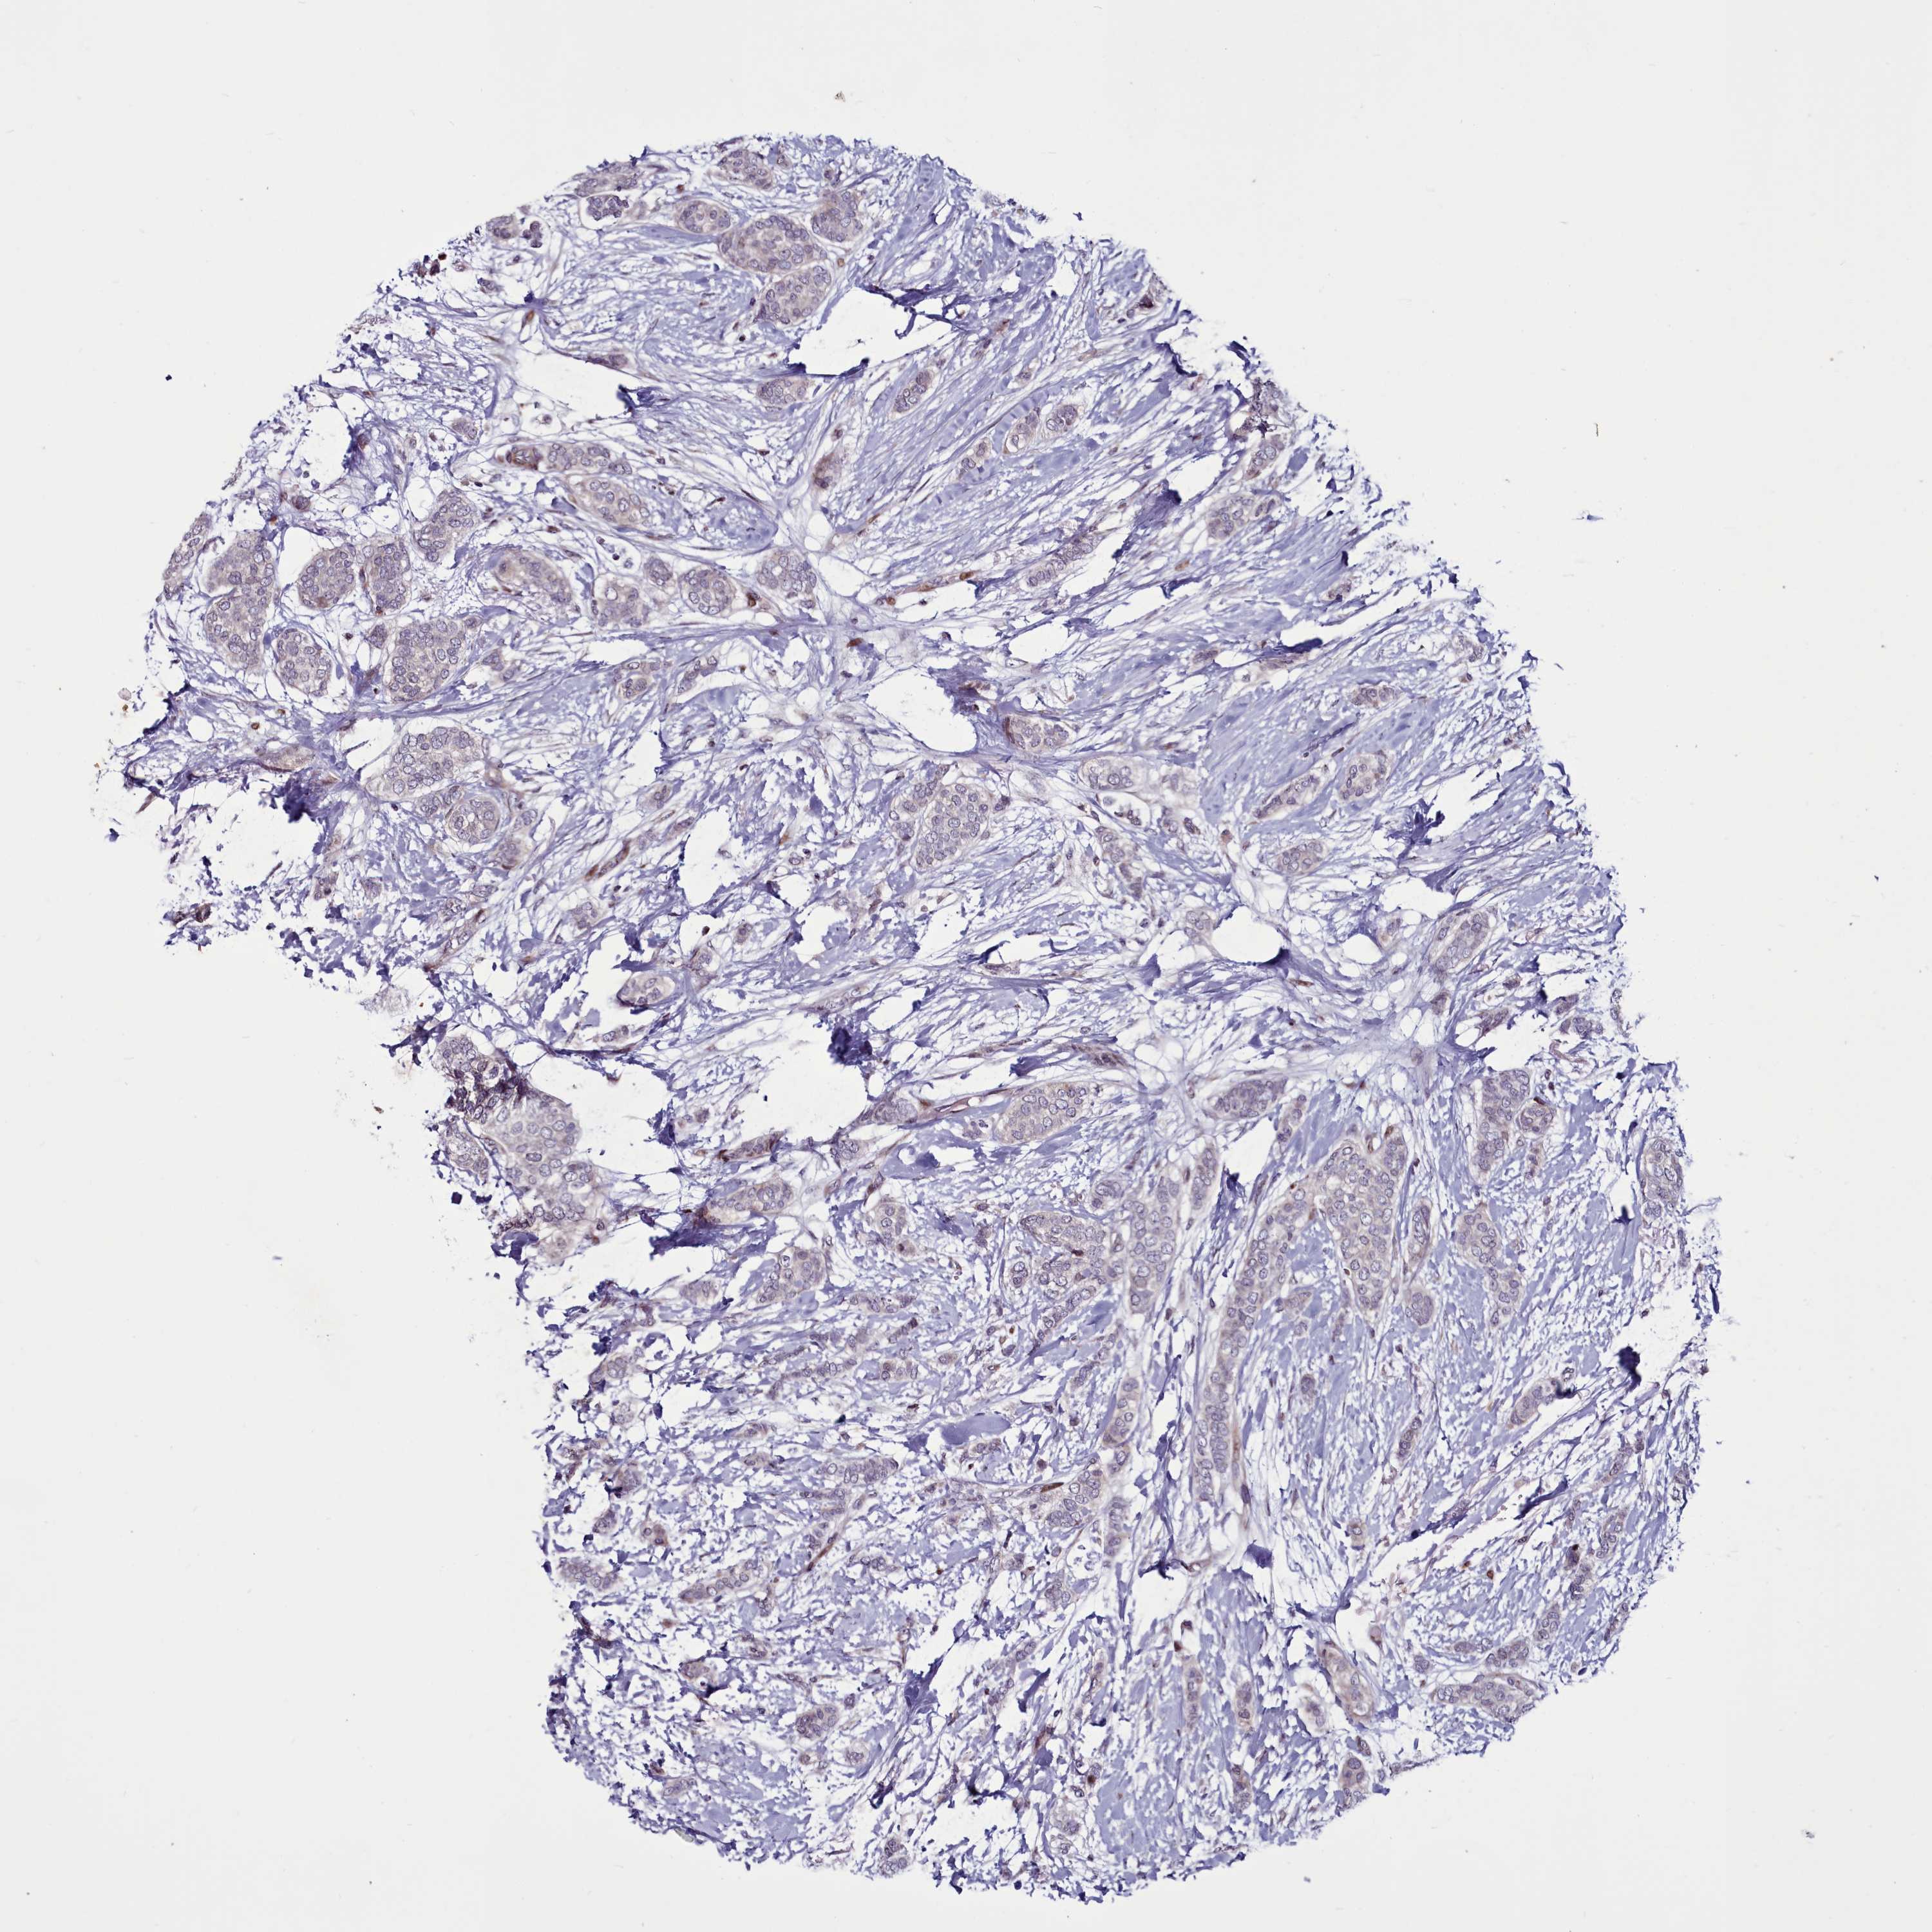

BRCA TCGA BRCA VALIDATION PROTEIN EXPRESSION

ANTIBODIES

AND

VALIDATION